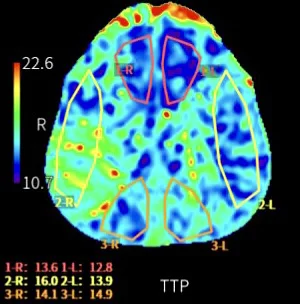

CT灌注成像确认:右侧大脑前动脉供血区TTP延长,血流下降。

术后一周CT灌注确认:双侧大脑前动脉供血区TTP对称,右侧供血改善。